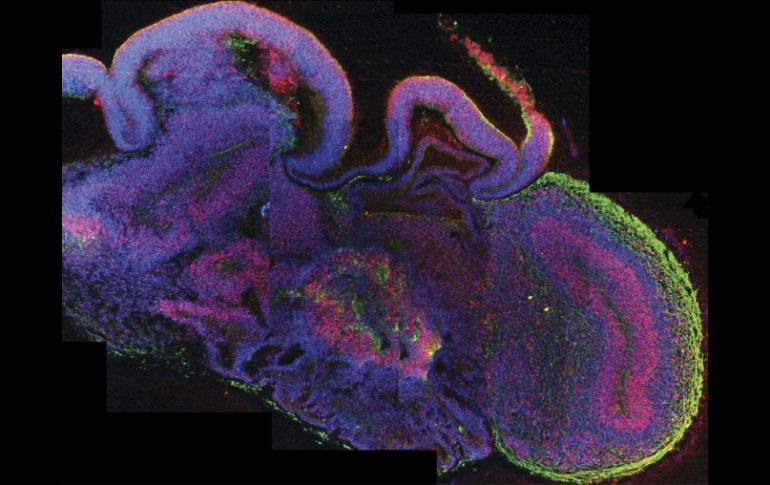

Tecnología | Los microcerebros están formados por diferentes tejidos dispuestos en capas Desarrollan cerebros humanos a partir de células madre Los microcerebros están formados por diferentes tejidos dispuestos en capas Por: EFE 28 de agosto de 2013 - 18:39 hs Imagen del desarrollo del cerebro, con todas las células en azul, las células madre neuronales en rojo, y las neuronas en verde. EFE / LONDRES, INGLATERRA (28/AGO/2013).- Un equipo de científicos europeos ha desarrollado pequeños cerebros humanos tridimensionales, de cuatro milímetros de diámetro, a partir de células madre pluripotentes que ayudarán a profundizar en el estudio de las enfermedades neurológicas, informó hoy la revista científica "Nature". Estos órganos artificiales, fruto de una investigación conjunta de la Universidad de Bonn (Alemania) y el Instituto de Biotecnología Molecular de Viena (Austria), aportan importantes avances sobre el desarrollo del cerebro durante las etapas más tempranas y sus patologías. La complejidad del cerebro humano ha impedido avanzar más en el estudio de las enfermedades neurológicas, por lo que era "necesario un sistema celular que simulara las complejas características de este órgano para estudiarlo en profundidad", explicó a los medios el alemán Juergen Knoblich, jefe del proyecto. "Este planteamiento puede superar algunas de las limitaciones que encontramos cuando experimentamos con el cerebro de los animales, ya que no comparte las mismas peculiaridades del cerebro humano", añadió el científico. Estos microcerebros, que incluyen la corteza cerebral que cubre los dos hemisferios, están formados por diferentes tejidos dispuestos en capas, cuya organización guarda muchas semejanzas con la de un cerebro en sus etapas más tempranas de desarrollo. Para demostrar la utilidad de este sistema celular, los científicos analizaron las diferentes enfermedades neurológicas que tienen lugar cuando el cerebro se encuentra en pleno desarrollo, como la microcefalia. Este trastorno neurológico, que carece de un tratamiento para revertir sus síntomas, provoca que el tamaño de la cabeza de las personas afectadas sea considerablemente menor al que debería tener en relación con su edad y sexo. A partir de células madre pluripotentes, el equipo de investigadores añadió al sistema inicial una serie de células procedentes de pacientes que padecían microcefalia para obtener un cerebro característico de una persona con esta enfermedad. Los científicos encontraron así que en los cerebros con esta dolencia las células precursoras de las neuronas dejaban de proliferar demasiado pronto, un defecto que podría explicar algunas de las causas de la microcefalia. "Este fenómeno no tiene lugar de la misma forma cuando experimentamos con ratones, ya que ningún animal presenta la misma expansión neuronal que el ser humano", concluyó Knoblich. Estos pequeños órganos artificiales no presentan las mismas funciones mentales que un cerebro humano corriente, si bien el grupo de científicos no descarta progresar en esa línea, así como profundizar en otro tipo de enfermedades neurológicas. Temas Ciencia médica Cerebro Células madre Lee También Estudio chino revela una mutación que eleva riesgo de alzhéimer NASA confirma si el cometa 31/ATLAS amenaza la vida en la Tierra o no Conmociones cerebrales, la cuarta lesión más frecuente en partidos de la Conmebol ¿Cómo se forman los recuerdos en la mente? Recibe las últimas noticias en tu e-mail Todo lo que necesitas saber para comenzar tu día Registrarse implica aceptar los Términos y Condiciones